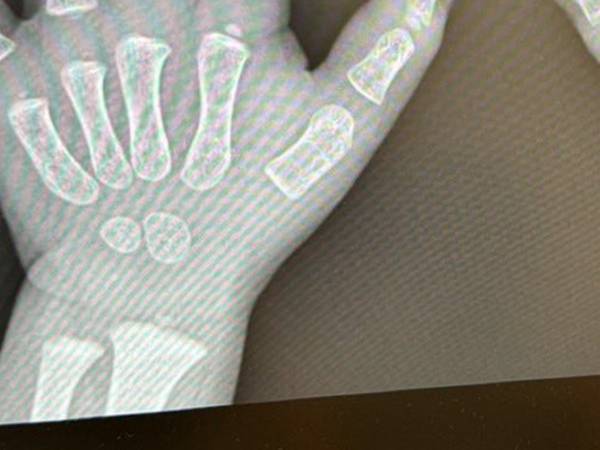

理由が分かる、実際のレントゲン写真をご覧ください。

か、かわいすぎる!

そこには発達途中の骨がはっきりと写っており、レントゲン写真ではあるものの、ムチッとした肉感が伝わってきます…。

我が子のかわいさを熟知しているココ3さんでも、骨格までかわいいとは驚いたことでしょう。なおさら、愛おしさがこみ上げますね!